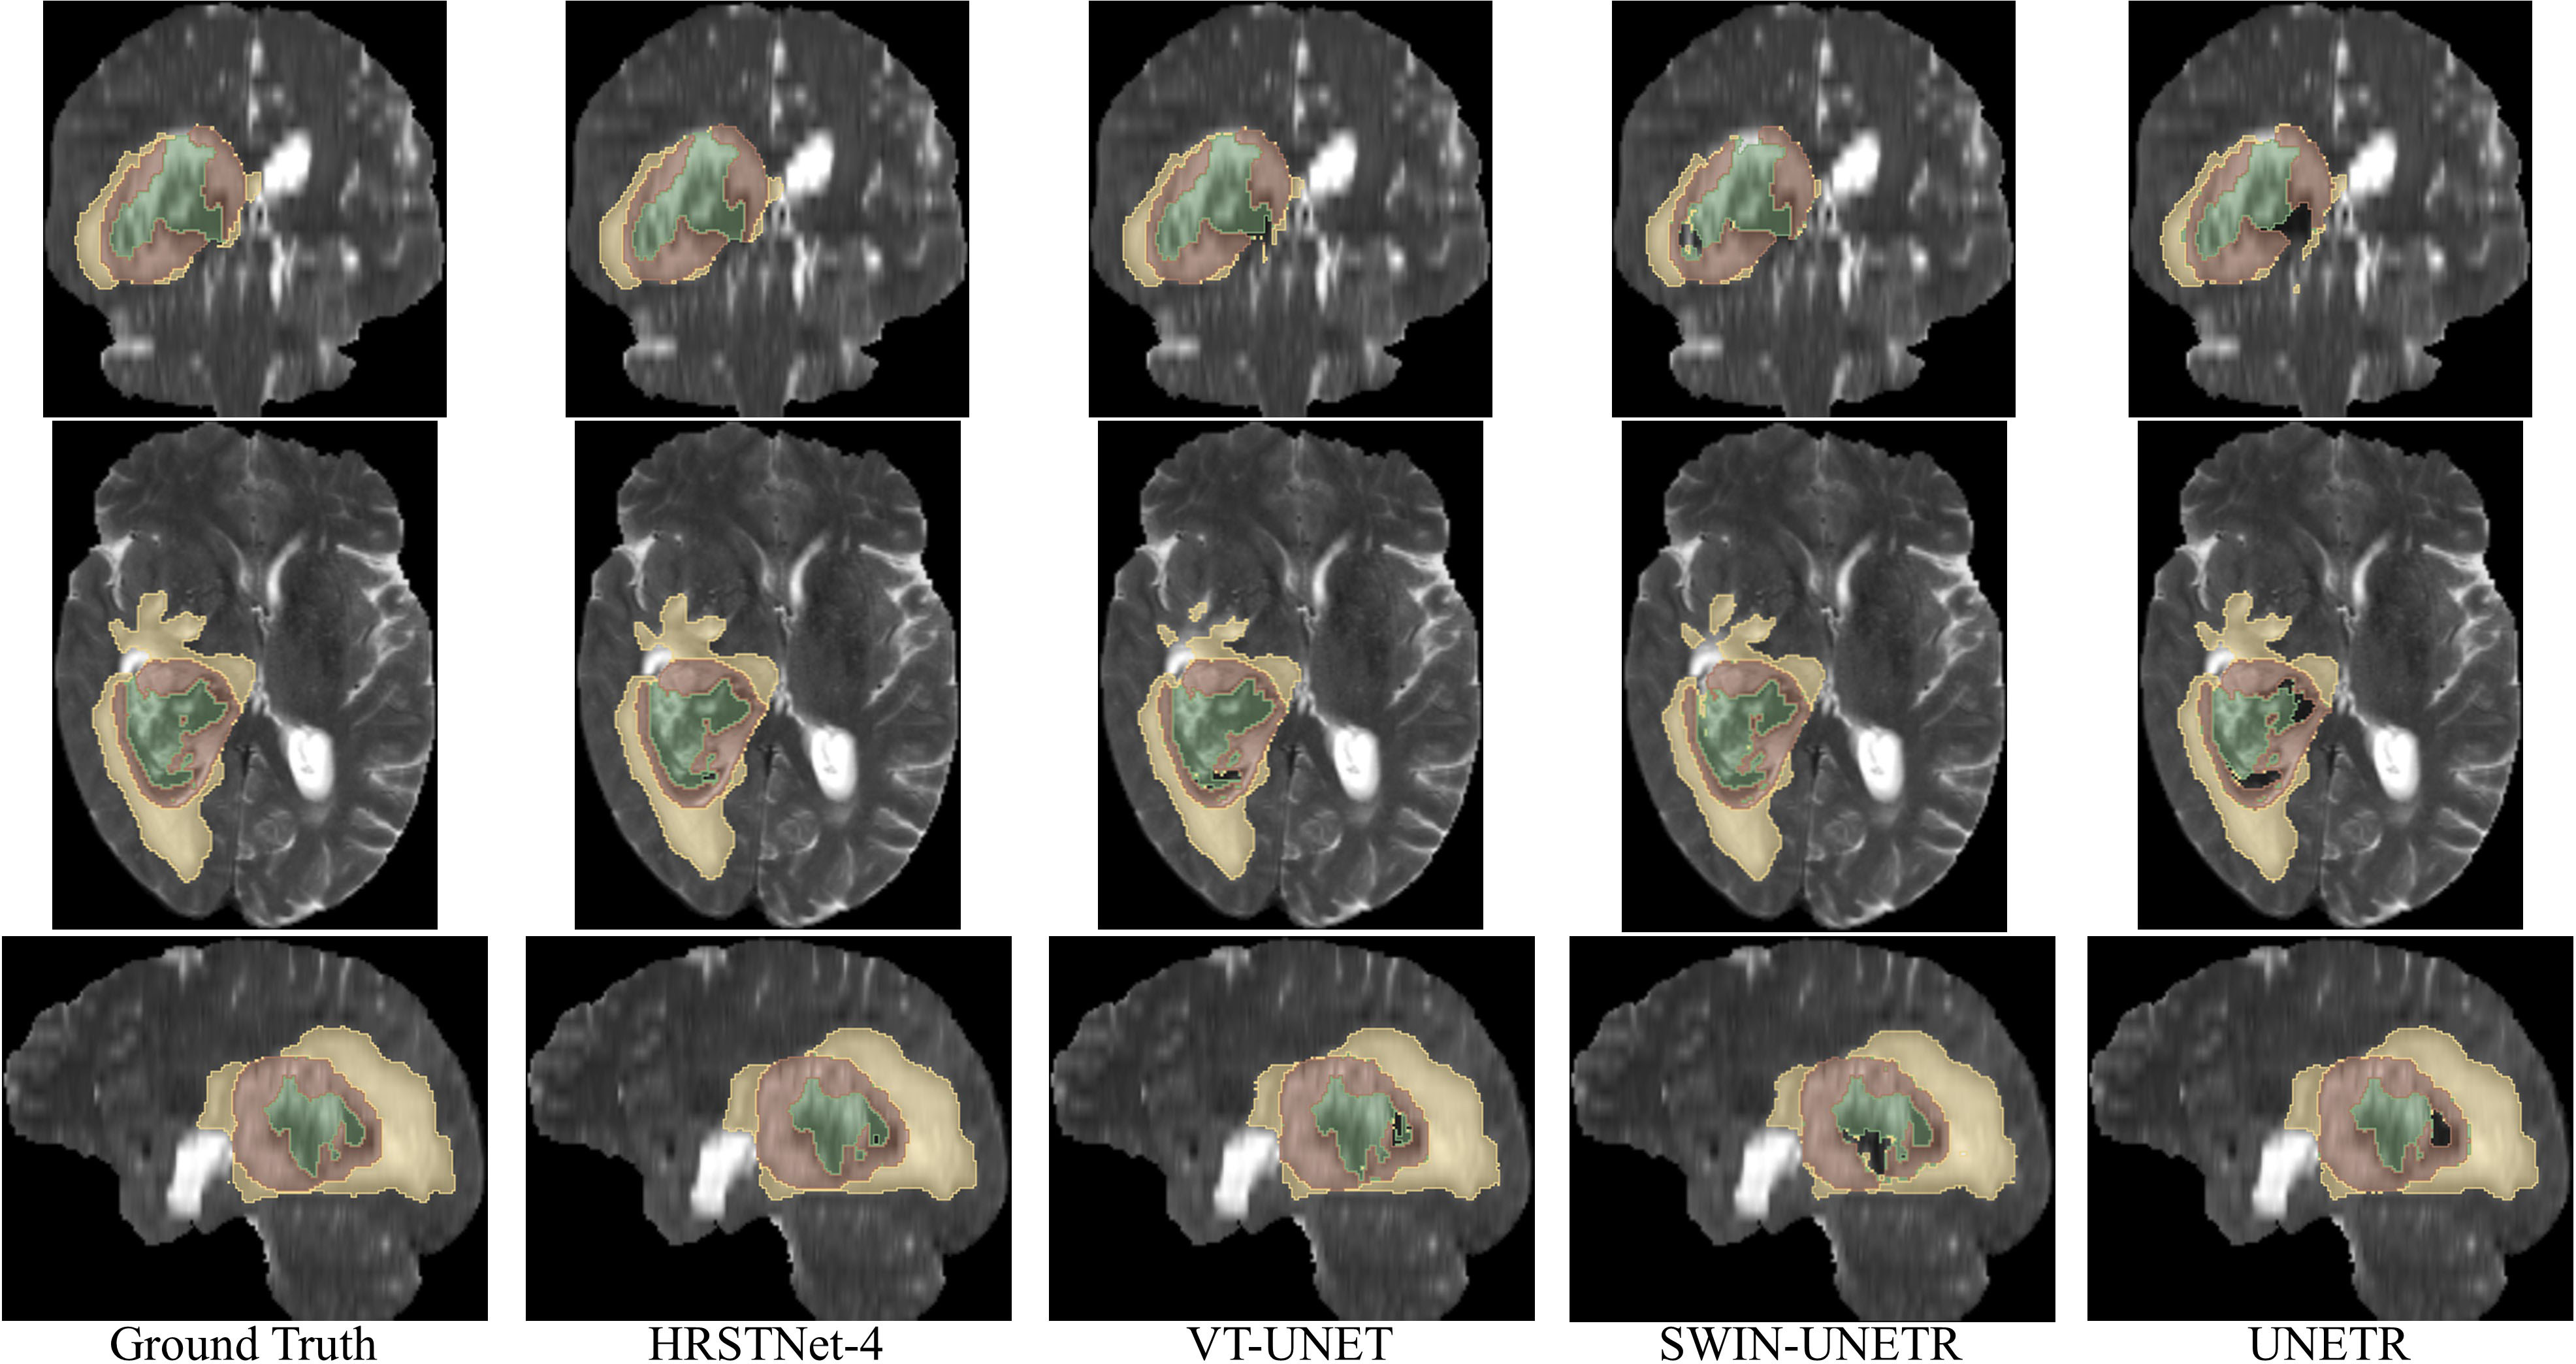

Fig. 3 shows the visualization of the segmentation results on BraTS 2021, from which we visually find that the segmentation results of HRSTNet-4 are better than those of the Transformer-based UNet-like architecture.

Figure 3: Visualizing of the segmentation results on BraTS 2021. Row 1 shows the coronal view of the segmentation results, row 2 illustrates the axial view of the segmentation results, and row 3 demonstrates the segmentation results of the sagittal view. The colors of the green, brown, and yellow represents the necrotic tumor core (NCR), enhancing tumor (ET), and the peritumoral edematous (ED), respectively.